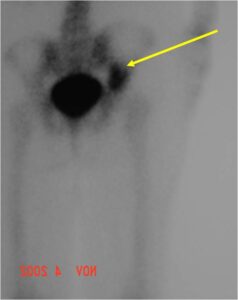

Radiology emulates pathology: Biphasic Tumor

- One region low grade chondrosarcoma

- Second more aggressive area with bone destruction, lysis of calcification, soft tissue mass

- Cortical permeation and a soft tissue mass in 70% of cases

Ill-defined, lytic intraosseous lesion

- Or extraosseous soft tissue mass

- Devoid of calcifications in continuity with lesions having the features of a cartilaginous tumor

Characteristically abrupt transition between chondroid tumor and dedifferentiated, lytic component